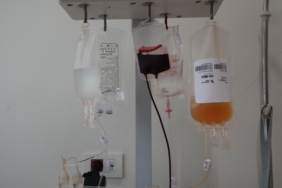

Şu dönem, günlük vaka sayısında Almanya, İtalya, Fransa gibi gelişmiş Avrupa ülkelerinde 100 binleri geçen vakaların görüldüğünü ifade eden Koca, “Bizde ise giderek artan bir vaka sayısı olduğunu görüyoruz. Vaka sayısının artışıyla birlikte hastane yükü aynı oranda artmıyor. Vaka sayısı artışı şu an günlük 40 katına kadar çıkmış durumda. Hastane yükü ise şu an 3 kat kadar arttı. O anlamda ciddi bir hastane yükümüzün olmadığını çok rahat söyleyebiliriz. Yoğun bakımlarda da bu artışların belirgin ve ciddi olmadığını görüyoruz. Artışın aynı oranda olmadığını rahatlıkla söyleyebiliriz.” diye konuştu.

Vatandaşların bu dönemde hatırlatıcı güncel dozlarını mutlaka yaptırmalarını, özellikle 50 yaş üstü, kritik, riskli olanların aşıyı hassasiyetle uygulamalarını önemsediklerini vurgulayan Koca, “Bir de yine riskli, 50 yaş üstü, kronik hastalığı, ek hastalığı olan kişilerin de kalabalık ortamlarda maskelerini her zaman olduğu gibi takmalarını ısrarla öneriyoruz. Aşı olmak isteyen vatandaşlarımızın TURKOVAC aşısını olmayı önemsemelerini isterim. Yerli aşımız oldukça etkili. Sonuçlarından memnunuz. TURKOVAC tercihinde ve önerisinde hassasiyet gösterelim.” açıklamasında bulundu.

“Kalabalık ortamlarda riskli isek maskeyi takmamız gerektiğini, eğer kendimizde üst solunum yolu enfeksiyonu belirtisi mevcut ise başkasına bulaştırmamak için maskeyi zaten takmak gerektiğini biliyoruz. Riskli olan kişilerin eğer bir belirti varsa erken dönemde testlerini yaptırıp, eğer pozitifse o durumda ek hastalığı varsa ilaca başlama durumu söz konusu olabilir. Dolayısıyla elimizde ilacımız var, aşımız var. Kişisel tedbirlere uyarak Kovid’le yaşamayı artık öğrendik. Kovid bitti mi? Bitecek mi? Bitmeyecek. Bir influenza gibi düşünün. Zaten son dönemde de belirtileri grip benzeri seyrediyor. Daha çok boğaz ağrısı, burun akıntısı ve ateşle seyrediyor ve beraberinde de kas ağrılarını görüyoruz. Ağır influenza tablosu gibi gelişiyor. Ama ek hastalığı olanlarda bu belirtiler daha belirgin, hastaneye yatışa kadar giden sonuçlara sebep olabiliyor. Onun için biraz daha dikkatli olmamız lazım.”